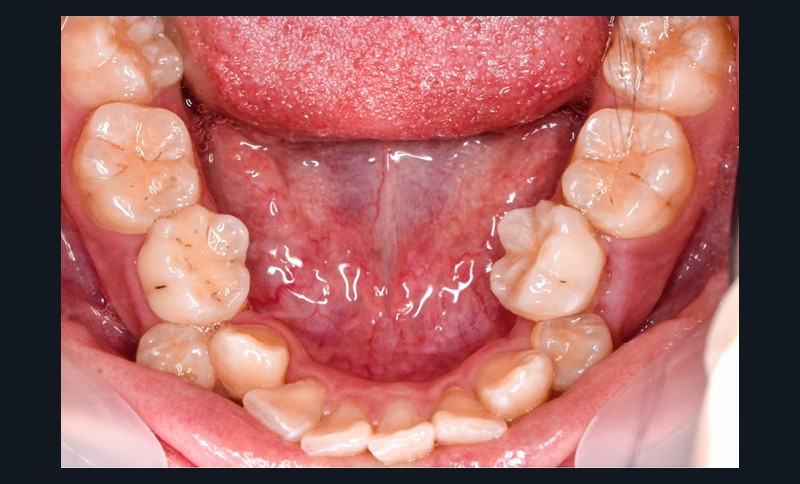

Une patiente âgée de 12 ans se présente en consultation, motivée par la position de son incisive centrale maxillaire, décrite comme « en avant », marquée par une dyschromie et une mobilité de grade 2 selon Muhlemann. L’examen clinique montre l’absence de 23 sur l’arcade, une dysharmonie dents-arcade marquée, un surplomb accentué, et une déviation des milieux inter-incisifs, conséquence du comblement spontané de l’espace de 23. L’ensemble s’inscrit dans un contexte de Classe I d’Angle molaire. L’orthopantomogramme révèle l’inclusion de 23, associée à une résorption radiculaire étendue aux deux tiers de 21. La 22 ne présente aucune altération visible.

La patiente, de profil normodivergent, présente une Classe I squelettique sans troubles fonctionnels (fig. 1-8).